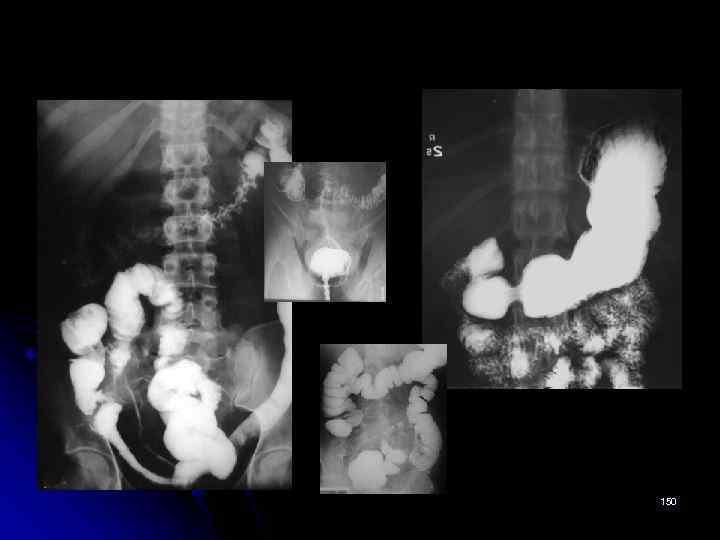

Скачать презентацию Рентгеновская семиотика заболеваний органов желудочно-кишечного тракта Кафедра лучевой Скачать презентацию Рентгеновская семиотика заболеваний органов желудочно-кишечного тракта Кафедра лучевой